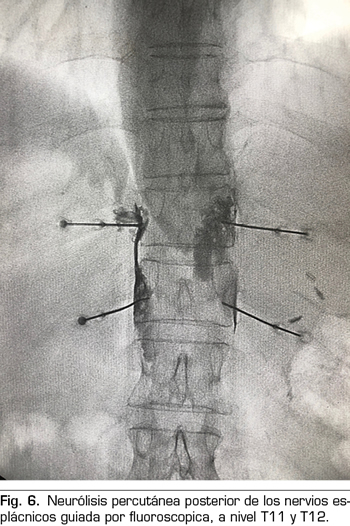

La ecoendoscopia ofrece la ventaja de una mayor visualización del plexo celiaco a corta proximidad, permitiendo una mayor precisión y seguridad en la administración del agente neurolítico y evitando la inyección en estructuras vasculares mediante el uso del Doppler (37) (Figura 5). No obstante, los trabajos que apoyan la neurólisis ecoendoscópica, considerada al igual que la técnica percutánea como una terapia de rescate, están limitados a estudios retrospectivos no controlados (38). Pauli y cols. publicaron un metanálisis que concluye que esta técnica consigue una reducción del dolor del 80 % en pacientes con cáncer de páncreas (39). Algunos estudios muestran un ligero descenso en el consumo de opioides, pero sin una fuerte evidencia científica.

NEURÓLISIS ECOENDOSCÓPICA DEL PLEXO CELIACO